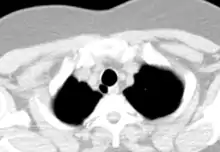

- CT scan of the thorax (axial lung window)

- CT scan of the thorax (coronal lung window)

- CT scan of the thorax (coronal mediastinal window)